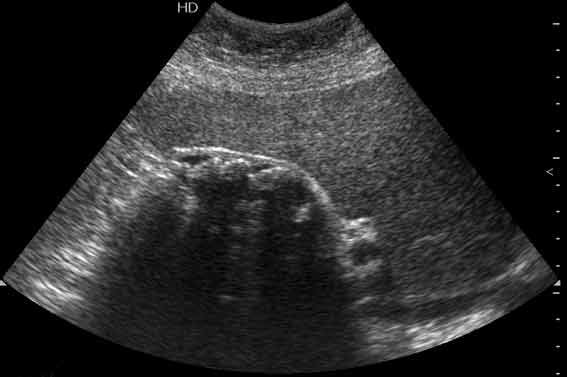

ЖКБ, холецистолитиаз. Вероятно, отключенный желчный пузырь.

УЗИ: ЖКБ, холецистолитиаз. Отключенный ЖП?